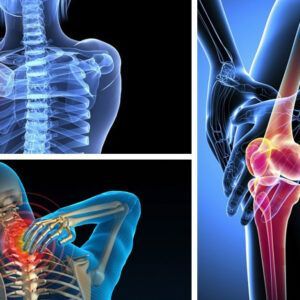

- Hỗ trợ xương khớp, gout